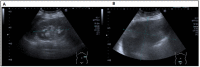

Mucinous cystadenomas are among the most common benign ovarian neoplasms. They are known for their massive size causing compressive effects ranging from pressure, pain, bloating, and urinary symptoms. Over time, these adnexal masses can lead to fatal complications, such as ovarian torsion or hemorrhage. Incidental findings of these tumors are common as many of these patients are asymptomatic. Pelvic examinations and imaging studies can be used to further diagnose symptomatic patients and aid physicians in developing an appropriate course of treatment. We report a rare case of a large mucinous cystadenoma, with a size of 25 × 25 cm and concurrent management of postmenopausal bleeding. We present the data from the admission of the patient to her discharge, including history and physical examination, diagnostic reports, transabdominal ultrasound, CT scan, surgical evaluation, and surgical-pathology reports. Abdominal pain can present in a variety of different scenarios, and ovarian masses only represent a small portion of the differentials. Mucinous cystadenomas constitute an even smaller percentage of these ovarian growths. As discussed in this case report, a large ovarian mucinous cystadenoma was compressing the surrounding structures resulting in a wide array of symptoms. The case describes the importance of extensive diagnostic evaluation and prompt surgical management of these ovarian tumors. It also brings attention to the significance of diagnosing a medical condition such as postmenopausal bleeding promptly to avoid potential negative outcomes.